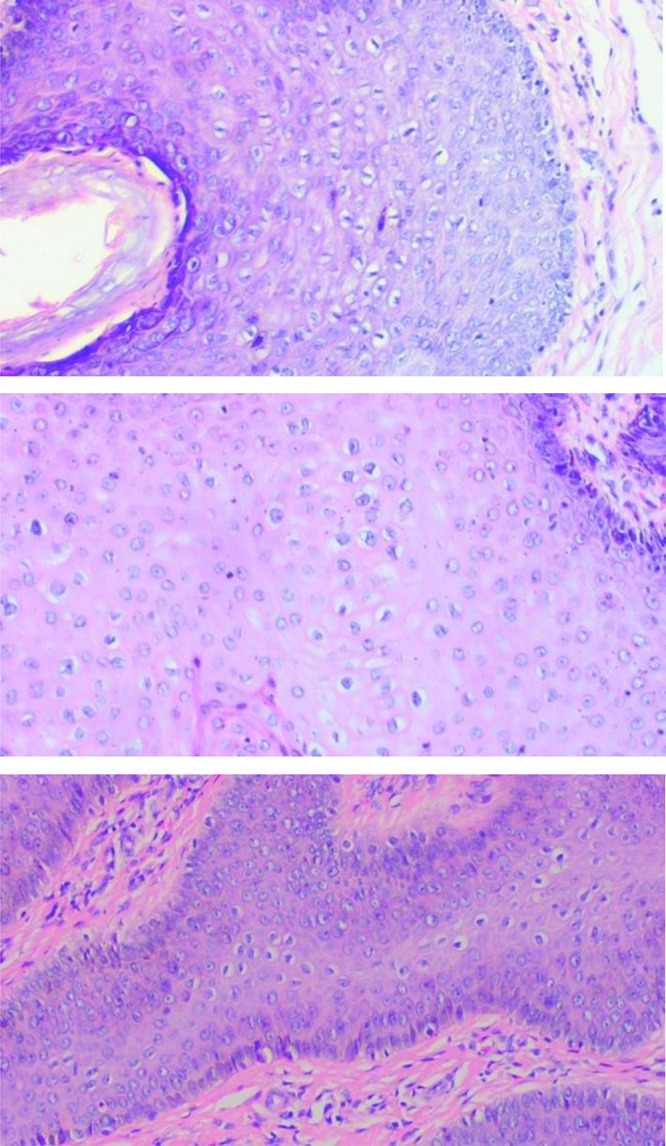

Extragenital warts caused by HPV types 6 and 11 are rarely reported. However, major risk factors for anogenital warts (AGW) include men who have sex with men (MSM) and Human Immunodeficiency Virus (HIV) infection. The incidence of extragenital warts among these populations has not been reported. This study presented a case report of a 33-year-old male with high-risk sexual behavior who showed symptoms of flesh-colored and hyperpigmentation papules. Furthermore, verrucous surfaces were observed at genital and extragenital. The patient had a history of using the same razor for pubic and armpit hair, bathing with a mesh scrub, and scratching the anal area. The histopathological result showed koilocytes, while polymerase chain reaction (PCR) examination for both genital and extragenital lesions confirmed HPV type 6 and 11. This represented the first reported case describing the incidence of extragenital and AGW caused by HPV types 6 and 11. The transmission of extragenital warts was facilitated through fomites autoinoculation, particularly in the immunocompromised condition induced by HIV, which was common among MSM. Extragenital warty-like lesions were considered as warts caused by HPV type 6/11, in HIV-infected persons, specifically MSM.

Abstract Image